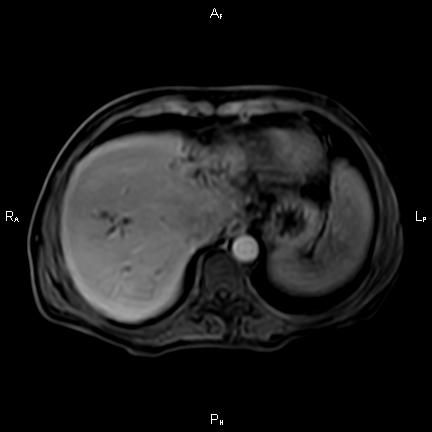

ΚΛΙΝΙΚΑ ΣΤΟΙΧΕΙΑ – ΙΣΤΟΡΙΚΟ

Ανώδυνος ίκτερος και παθολογικά ηπατικά ένζυμα. Ιστορικό πιθανής σκληρυντικής χολαγγειίτιδας

ΑΠΕΙΚΟΝΙΣΤΙΚΟΣ ΕΛΕΓΧΟΣ

Μαγνητική τομογραφία.

Παρουσία